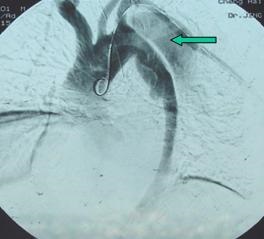

▲ 实例:术中造影可见破口

▲ 单纯覆膜支架植入覆盖破口